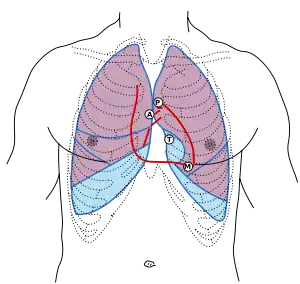

First heart sound: caused by atrioventricular valves – Mitral (M) and Tricuspid (T).

Second heart sound caused by semilunar valves – Aortic (A) and Pulmonary/Pulmonic (P).

Surface anatomy

The aortic area, pulmonic area, tricuspid area and mitral area are areas on the surface of the chest where the heart is auscultated.[6] Heart sounds result from reverberation within the blood associated with the sudden block of flow reversal by the valves closing. Because of this, auscultation to determine function of a valve is usually not performed at the position of the valve, but at the position to where the sound waves reverberate.

| Aortic valve (to aorta) | right second intercostal space | upper right sternal border |

| Pulmonary valve (to pulmonary trunk) | left second intercostal space | upper left sternal border |

| Erb's point | Left third intercostal space | left sternal border |

| Tricuspid valve (to right ventricle) | left fourth, fifth intercostal spaces | lower left sternal border |

| Mitral valve (to left ventricle) | left fifth intercostal space | left midclavicular line |